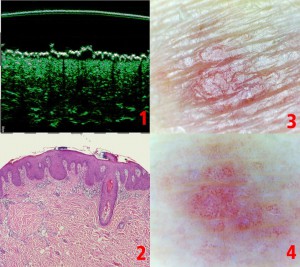

-Υπέρηχος Υψηλής Συχνότητας (HFUS) και Ιστολογία

-Μελάνωμα

-Μέτρηση επιπέδων Breslow και Klark σε έμβιο οργανισμό (IN VIVO)

-Διαφοροποίηση τύπων βασικοκυτταρικού καρκινώματος